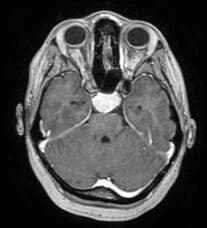

"התווכחתי איתם, הבנתי שזה לא קשור לעומס נפשי. אבל לא ידעתי מה זה. הם לא ראו שום דבר סביב העין עצמה, ולכן התעקשו שאין כלום. מהצד שלי לא ידעתי שאני צריכה לבקש בדיקת CT. אני אמורה לסמוך על הרופאים. לא האמינו לי שיש בעיה, חשבו שאני עובדת עליהם. רק כשאבא שלי הגיע לבית חולים והתעקש שאעשה את כל הבדיקות, קיבלתי הפניה לבדיקת CT. הם לא האמינו שימצאו משהו, אבל ישר ראו את זה בבדיקה. היה כמעט 3 ס"מ של גידול".

"הגידול שבו מדובר הוא גידול בשם מנינגיומה", מסביר ד"ר מרגלית. "זה גידול של מעטפות המוח שגדל סביב או מתחת למוח על בסיס הגולגולת. הוא יכול לערב כל מיני דברים שנמצאים בסביבתו. במקרה הזה, הוא לוחץ את עצבי הראייה. הוא יכול לגרום להפרעת ראייה קשה".

"בבדיקת CT היו במאה אחוז רואים את הגידול. זה גידול שגדל באיטיות לאורך חודשים ושנים. אין ספק שהגידול היה שם כבר שנתיים - שלוש עוד לפני האבחון. כשהוא גדל, יש פגיעה קשה בעצבי הראייה. עדיף שתהיה בדיקת CT מיותרת ולא נפספס את אלו שכן יש להם גידול, צריך לשלול ולהוריד מהפרק את האופציה הזו - ואחר כך להמשיך בחיפוש של דברים אחרים".

"לא. מדובר בגידול התוך גולגולתי הראשוני הכי שכיח באדם מבוגר. המצב בו הוא מערב את עצבי הראייה לא שכיח, אבל גם לא נדיר וניתחתי עד היום מאות אנשים שהיתה להם מעורבות של עצבי הראייה עם מנינגיומה. אני מומחה לנושא והידיעה שחולה כמו עדי קיבלה המלצה לעבור את הניתוח בחו"ל מטרידה ומיותרת. חשוב להעלות מודעות לזה שהגידולים האלה זו אחת מהאפשרויות לירידה בראייה שלא מוסברת בצורות אחרות. חשוב לדעת שהגידול לא כל כך נדיר".